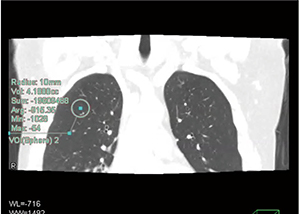

PhyZiodynamicsによるDynamic VOI解析だが、これは体積一定の球形VOIを肺内の任意の点に置くと、その中心点が呼吸ダイナミックCTの全時相で追跡され、VOI内の肺野濃度の自動計測ができる、というものである(図2)。VOI内の平均肺野濃度MLD(mean lung density)の変化は、吸呼気による肺容積の変化と等価であり5)、すなわち吸気時にはMLDが低下し、呼気時にはMLDが上昇する時間曲線を描くことができる。このDynamic VOI解析を、右肺3葉、左肺2葉において行ってみると、健常者においては当然ながらMLDの時間曲線はよく相似するが、重症COPDになると曲線の相似性が崩れ、各葉が時間的連動性を失ってバラバラに動く傾向があることが明らかになった(図3)。この結果は、学術論文として近日中に海外の学術雑誌より出版されるが、これまで種々の理学所見・画像検査などで明らかになっている、COPD患者での換気の不均一性・横隔膜の異常運動などに対応した、「肺葉の呼吸運動の同時性の消失」を世界で初めて明らかにしているものと考えられ、COPDの病態生理学的な画像解析において新たな扉を開いたものと確信している。

図2 PhyZiodynamicsによるDynamic VOI計測の例

図3 非COPD患者、COPD患者におけるDynamic VOI計測の結果(右上葉・右下葉のみ提示)

COPD患者では平均肺野濃度(MLD)曲線がほぼ逆の形態を示し、上葉と下葉の呼吸運動が連動していない。